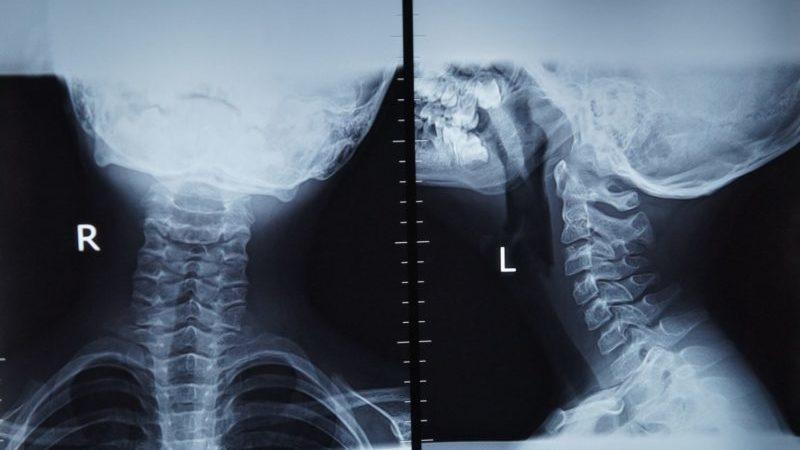

Диагностика

Сразу после рождения новорожденного осматривают не только акушер-гинеколог, но и неонатолог. Этот специалист оценивает жизненные показатели малыша, проводит осмотр и разрабатывает план наблюдения за ним на протяжении его пребывания в медицинском учреждении.

В большинстве случаев признаки натальной травмы шейного отдела можно заметить сразу после родов. Во время осмотра врач может обнаружить аномалии в длине данного сегмента позвоночника.

Также шея может быть отечной и гиперемированной, а напряжение наблюдается как в цервикальных, так и в затылочных мышцах. Фиксация шейного отдела в одном положении и его искривление являются наиболее яркими признаками натальной травмы.

Наличие этих симптомов требует проведения рентгенографии, УЗИ и допплерографии, которые помогут подтвердить диагноз.